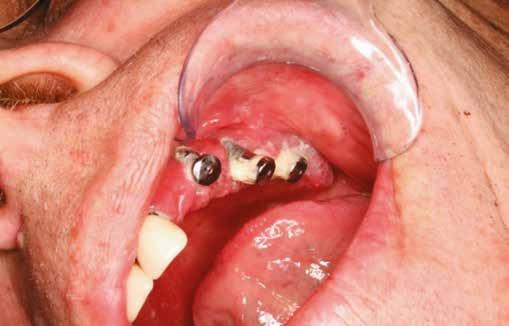

A 2.5-ös fog mentén periotómot haszáltunk, hogy átvágjuk a periodontális rostokat, így a fogat kilazítottuk, hogy ezzel is csökkenthessük a fogó által végzendő laterális mozgások szükségességét, illetve hogy a környező csontot is a legnagyobb mértékben megőrizzük. Nem volt elég csont (anélkül, hogy perforálnánk az arcüreg alapját) ahhoz, hogy abban stabilizáljuk az implantátumot, úgy döntöttünk, hogy behelyezünk egy ∅ 5.0 x 12 mm-es Straumann® BLX implantátumot közvetlenül az alveolusba, előfúrás nélkül. Az implantátum menetkialakítása lehetővé tette, hogy a kézidarabbal behajtva, 25 Ncm-es nyomatékot érjünk el, majd racsnis nyomatékkulcs segítségével juttattuk a végső pozíciójába, 80 Ncm-es behajtási nyomatékot mérve (3. és 4. ábrák).

A 2.6-os fog helyén egy 6 mm mély furatot készítettünk a gyártó előírása szerint, a puha csont protokoll lépéseit követve. Egy ∅ 5.0 mm × 6 mm Straumann® BLX implantátumot helyeztünk be 50 Ncm-es behajtási nyomatékkal (5. ábra)

A 2.7-es fog helyénél egy disztális irányú, 14 mm mély, ferde előfúrást végeztünk, elkerülve a sinus maxillarist a tuber csontkínálatának felhasználásával. Egy ∅ 5.0 mm x 14 mm Straumann® BLX implantátumot helyeztünk be, 50 Ncm-es behajtási nyomatékkal (6. ábra)

Mind a három implantátumba gyógyulási csavar került, ezzel elkerültük az újabb sebészi beavatkozás szükségességét.

Tovafutó varrattal zártuk a sebet az ínyformázó csavarok körül (7. és 8. ábrák).